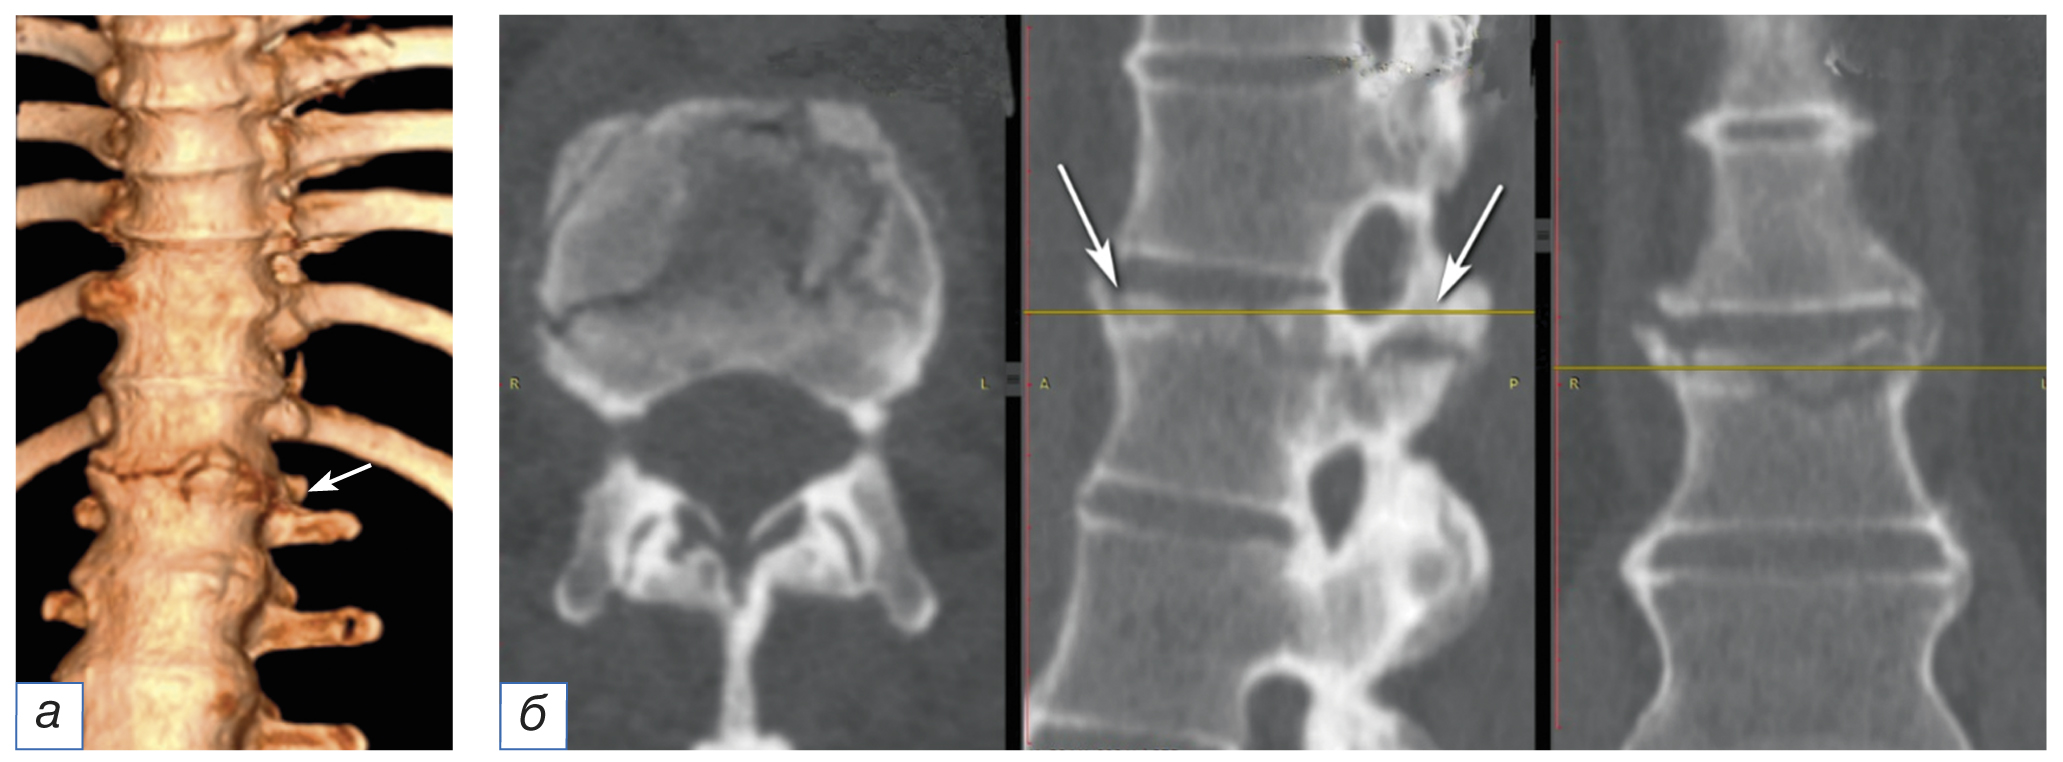

Послеоперационный период протекал благополучно. Болевой вертеброгенный синдром и клинико-неврологические расстройства регрессировали в течение 2 суток после оперативного лечения. Пациент активизирован на третьи сутки, грудопоясничный отдел позвоночника фиксирован ортопедическим корсетом. Внешняя иммобилизация осуществлялась в течение 4 месяцев. Трудоспособность восстановлена полностью. На контрольном осмотре спустя 6 месяцев после выписки пациент жалоб не предъявляет, работает по основной специальности, в социальной сфере реабилитирован. При МСКТ грудопоясничного отдела позвоночника определяется состоявшийся спондилодез на уровне ThXII–LI; стабильность опорных транспедикулярных винтовых элементов металлоконструкции удовлетворительная (рис. 3).

Рис. 3. Мультиспиральная компьютерная томографическая визуализация после проведённого декомпрессивно-стабилизирующего хирургического вмешательства: а — 3D-реконструкция грудопоясничного отдела позвоночника c 6-винтовой транспедикулярной фиксацией; б — аксиальный, в — сагиттальный, г — фронтальный срезы на уровне ThXII–LI с 6-винтовой транспедикулярной фиксацией.